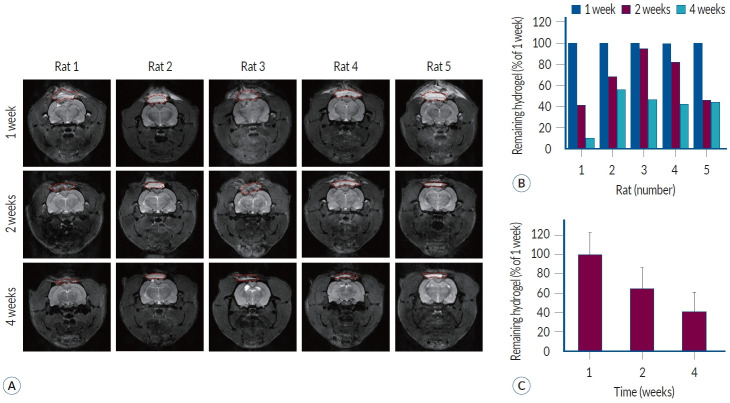

Methods: HA photosealants were applied to the incised dura in a rat craniectomy and durotomy. The HA photosealant quickly sealed the wound upon low-energy visible light exposure (405 nm, <5 seconds, < 1 J/cm2). The degradation of HA photosealants was tracked through serial MRI scans at 1, 2, and 4 weeks post-application. The remaining area of HA photosealants on the dura was measured using image processing program for volumetric analysis. Additionally, histopathological analyses were performed to evaluate the biocompatibility and effectiveness of the dural repair.

Results: The MRI and histopathological analyses showed that the HA photosealant achieved progressive degradation while successfully preventing CSF leakage without any adverse tissue reactions. The residual area of HA photosealants measured at 2 weeks ranged from 41.35% to 94.88%, with an average of 66.57%. At 4 weeks, a more distinct degradation pattern was observed compared to 2 weeks, showing a residual area of 10.28% to 56.11%. The HA photosealant maintained structural integrity until dural regeneration was completed.